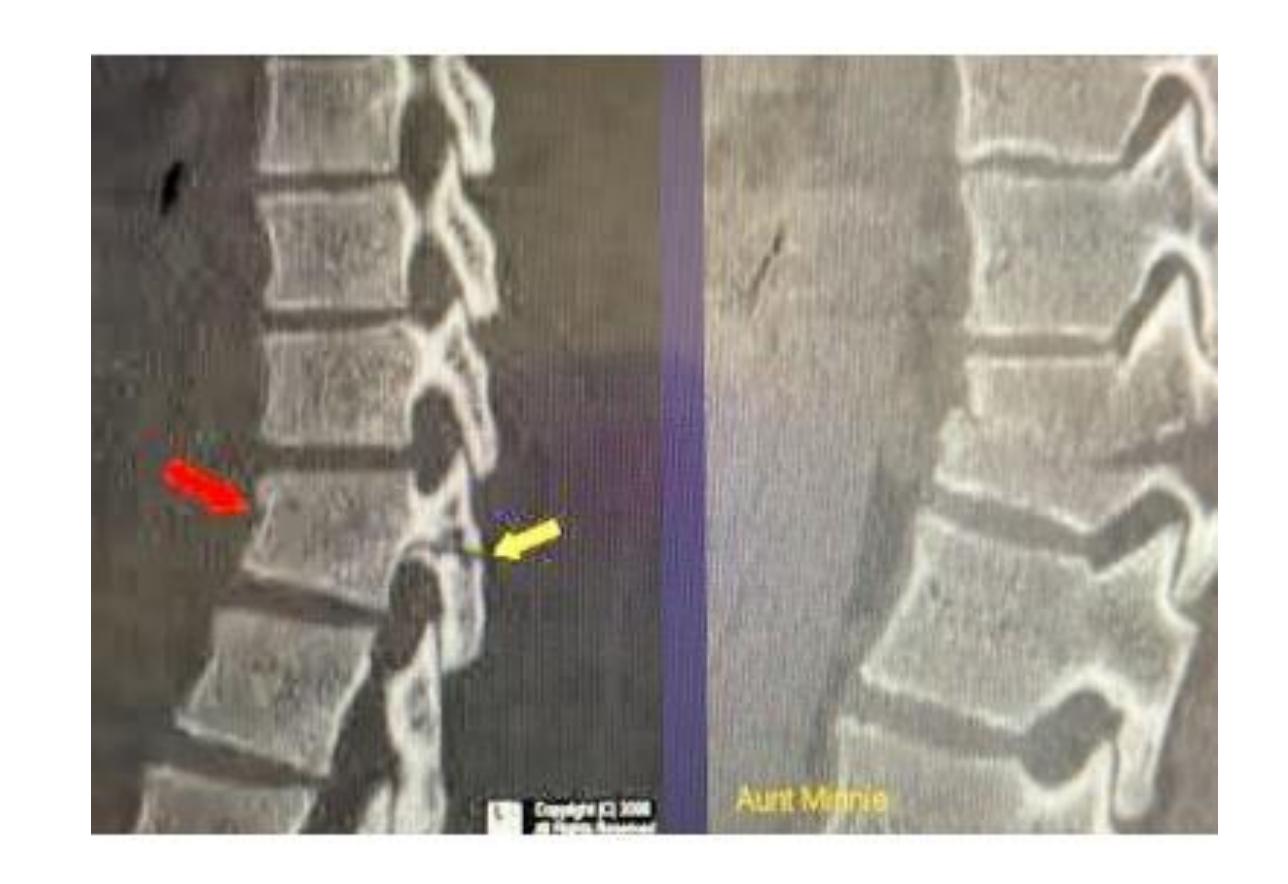

Spondylolisthesis

Lady came to the clinic complaining of long standing low back pain

Description Lateral x-ray of lumbar spine showing a fracture in the pedicle & slipped L4 over L5

Diagnosis: Spondylolisthesis

Diagnosis: Spondylolisthesis Next step? Oblique view - to see Scotty dog

Findings? X-ray of cervical spine should include all C vertebrae and T1. Anterior slippage of C4 over C5 and pars-interarticularis fracture (decapitated scotty dog)

Diagnosis? Pars interarticularis fracture (decapitated scotty dog)

Anterior displacement of L4 over L5, pars interarticularis disruption, osteopenia

Nerve compression may cause inability to control bowel and bladder sphincter, chronic pain and numbness